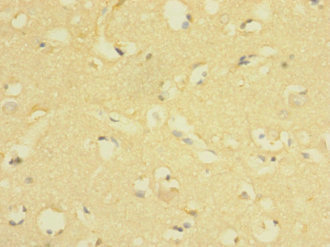

Immunohistochemistry of paraffin-embedded human brain tissue using CSB-PA850317ESR1HU at dilution of 1:100